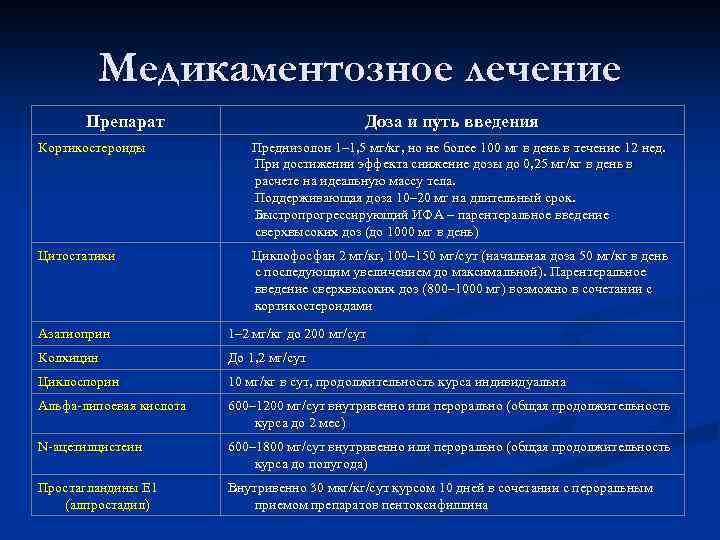

Медикаментозное лечение Препарат Доза и путь введения Кортикостероиды Преднизолон 1– 1, 5 мг/кг, но не более 100 мг в день в течение 12 нед. При достижении эффекта снижение дозы до 0, 25 мг/кг в день в расчете на идеальную массу тела. Поддерживающая доза 10– 20 мг на длительный срок. Быстропрогрессирующий ИФА – парентеральное введение сверхвысоких доз (до 1000 мг в день) Цитостатики Циклофосфан 2 мг/кг, 100– 150 мг/сут (начальная доза 50 мг/кг в день с последующим увеличением до максимальной). Парентеральное введение сверхвысоких доз (800– 1000 мг) возможно в сочетании с кортикостероидами Азатиоприн 1– 2 мг/кг до 200 мг/сут Колхицин До 1, 2 мг/сут Циклоспорин 10 мг/кг в сут, продолжительность курса индивидуальна Альфа-липоевая кислота 600– 1200 мг/сут внутривенно или перорально (общая продолжительность курса до 2 мес) N-ацетилцистеин 600– 1800 мг/сут внутривенно или перорально (общая продолжительность курса до полугода) Простагландины Е 1 (алпростадил) Внутривенно 30 мкг/кг/сут курсом 10 дней в сочетании с пероральным приемом препаратов пентоксифиллина